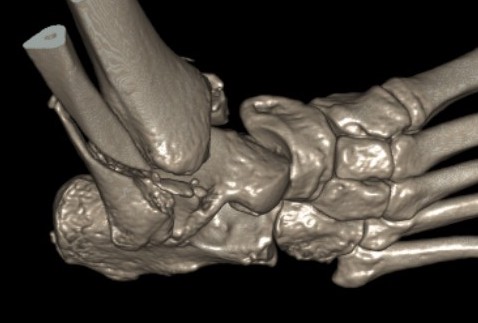

Injury patterns

TNJ +/- CCJ

Ligamentous +/- fracture dislocations

Fractures - trans-navicular / trans-cuboid

Imaging